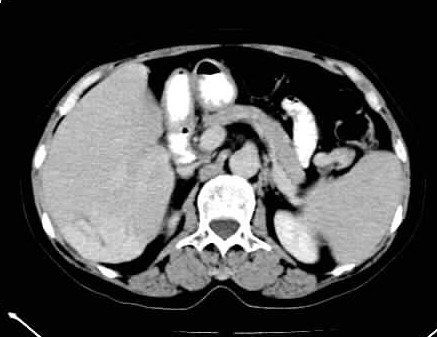

标题: CT24035:肝内占位

肝右后叶下段血管瘤,脾大。

考虑肝右叶后段血管瘤。